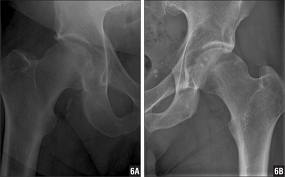

Kalça eklem sıkışma sorunları

Son 15 yıldır problemin farkındalığı artmaktadır.Kalça ekleminin topuz kısmındaki yuvarlaklığın farklı nedenlerle bozulması sonucu, yuva ile uyumsuzluğu olan hastalarda kasıkta ağrı ve kalça eklem hareketlerinde sınırlanmalara yol açar. Problemlerin tam adını koyup eklemin normal anatomisini sağlayacak şekilde, yeniden şekillendirme ameliyatları yapılmaktadır. Bu ameliyatlar artroskopik yada açık yöntemlerle gerçekleştirilebilir.